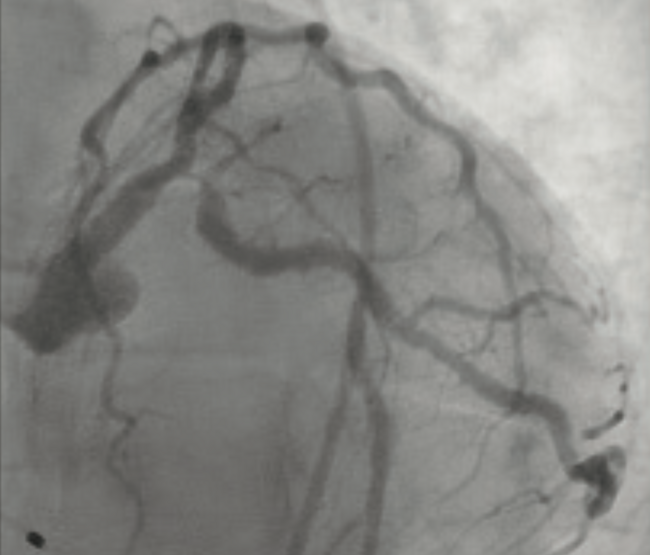

Since its approval, transcatheter aortic valve replacement (TAVR) has been an important innovation in the treatment of severe aortic stenosis and serves as an alternative to surgical aortic valve replacement (SAVR) in high-risk patients. In recent years, indications for TAVR have grown to include intermediate and even low risk patients. However, concomitant with increased utilization, complications of TAVR have also emerged. In 2015, as TAVR’s popularity was increasing, Makkar et al released a concerning report on subclinical leaflet thrombosis in patients who had undergone TAVR and SAVR. The study found reduced leaflet motion on four-dimensional, volume-rendered computed tomography (4DCT) in patients with both transcatheter and surgical bioprostheses. This condition, characterized by valve leaflet thickening and reduced motion on 4DCT, has been referred to as hypoattenuating leaflet thickening (HALT) and the more severe hypoattenuation affecting motion (HAM). Although the reduced motion was not associated with death, stroke, or myocardial infarction, it was associated with a higher incidence of transient ischemic attack and resolved with therapeutic anticoagulation.